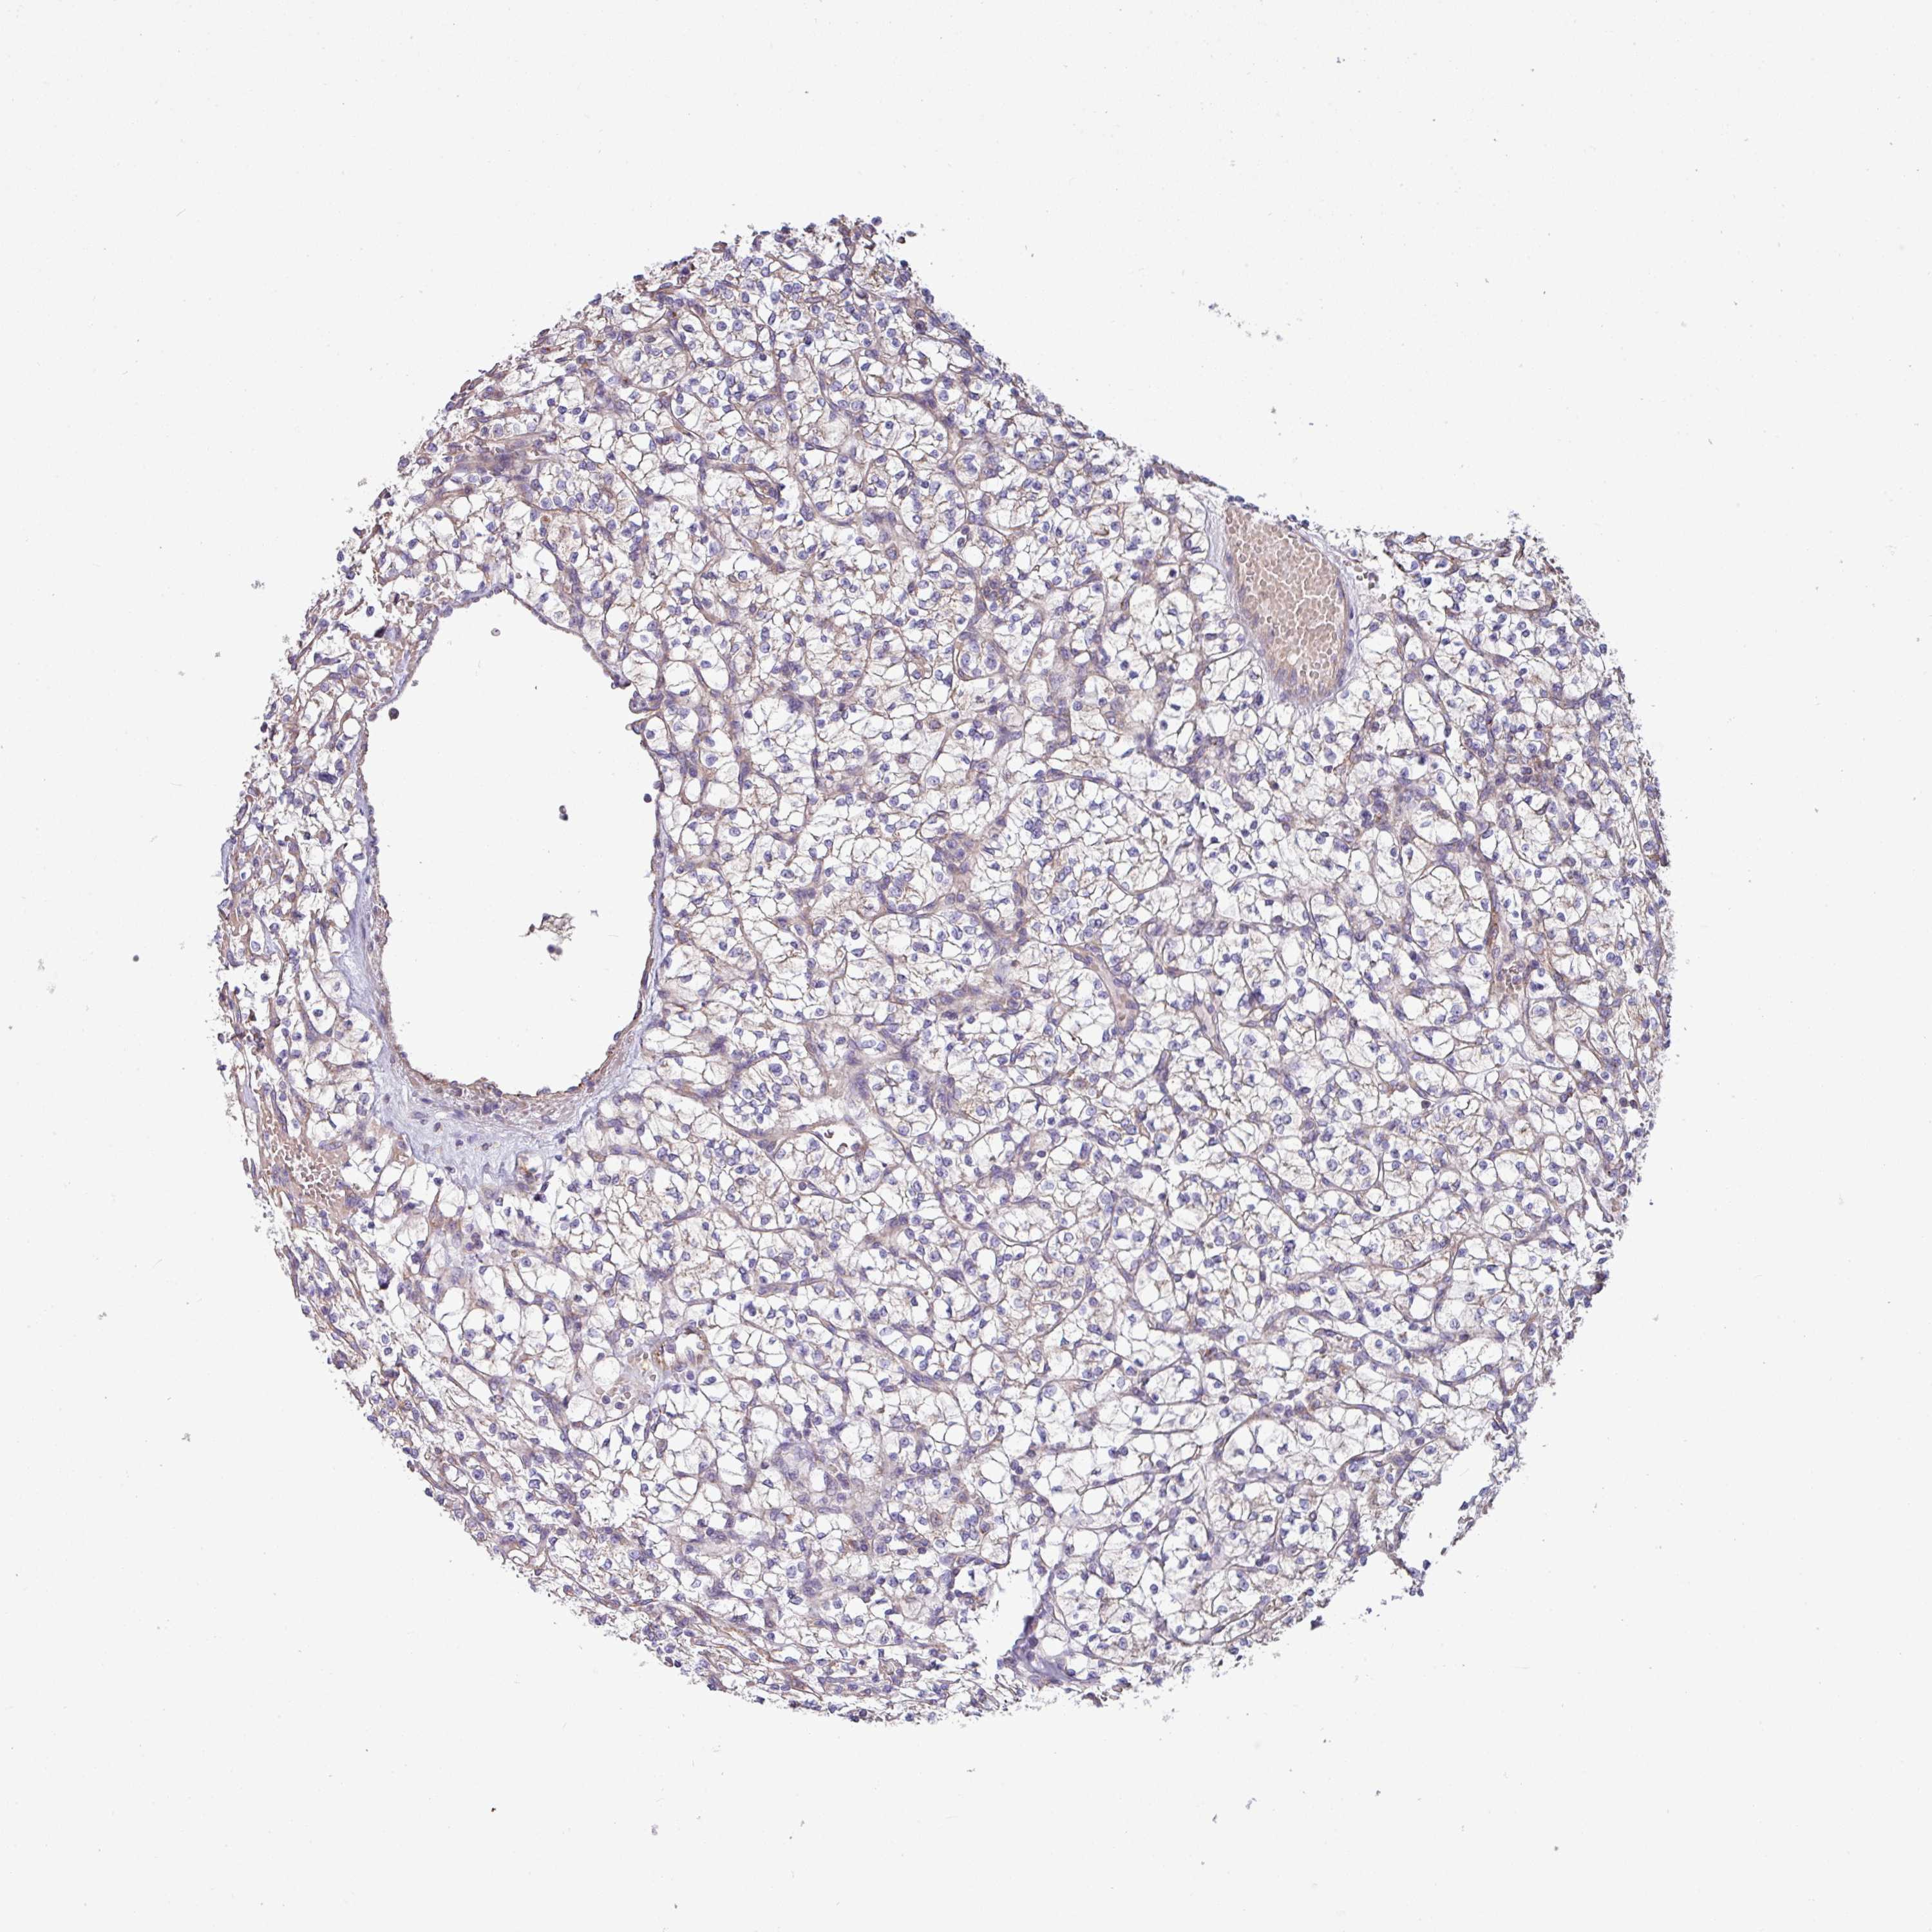

KIDNEY RENAL CLEAR CELL CARCINOMA (VALIDATION) - Interactive survival scatter ploti

The Survival Scatter plot shows the clinical status (i.e. dead or alive) for all individuals in the patient cohort, based on the same data that underlies the corresponding Kaplan-Meier plots. Patients that are alive at last time for follow-up are shown in blue and patients who have died during the study are shown in red.

The x-axis shows the expression levels (FPKM) of the investigated gene in the tumor tissue at the time of diagnosis. The y-axis shows the follow-up time after diagnosis (years). Both axes are complimented with kernel density curves demonstrating the data density over the axes. The top density plot shows the expression levels (FPKM) distribution among dead (red) and alive patients (blue). The right density plot shows the data density of the survived years of dead patients with high and low expression levels respectively, stratified using the cutoff indicated by the vertical dashed line through the Survival Scatter plot. This cutoff is automatically defined based on the FPKM cutoff that minimizes the p-score. The cutoff can be changed by dragging the vertical line or by entering a cutoff value in the square labeled "Current cut-off".

Under the Survival Scatter plot the p-score landscape (black curve; left axis) is shown together with dead median separation (red curve; right axis). Dead median separation is the difference in median mRNA expression between patients who have died with high and low expression, respectively. It is calculated as follows: median FPKM expression of dead patients with high expression - median FPKM expression of dead patients with low expression. This is intended to aid the user in visually exploring custom cutoffs and the associated p-scores and dead median separation.

Individual patient data is displayed and can be filtered by clicking on one or more of the category buttons on the top of the page. Categories describing expression level and patient information include: high, low, alive, dead, female, male and tumor stages. The scale of the x-axis can be toggled between linear and log-scale by clicking on the "x log" button. Mouse-over function shows TCGA ID, patient information and mRNA expression (FPKM) for each patient.

& Survival analysisi

Kaplan-Meier plots summarize results from analysis of correlation between mRNA expression level and patient survival. Patients were divided based on level of expression into one of the two groups "low" (under cut off) or "high" (over cut off). X-axis shows time for survival (years) and y-axis shows the probability of survival, where 1.0 corresponds to 100 percent.

PPM1J is not prognostic in Kidney Renal Clear Cell Carcinoma (validation)

TCGA RNA samplesi

RNA-seq data is reported as average FPKM (number Fragments Per Kilobase of exon per Million reads), generated by the The Cancer Genome Atlas (TCGA) .

Normal distribution across the dataset is visualized with box plots, shown as median and 25th and 75th percentiles. Points are displayed as outliers if they are above or below 1.5 times the interquartile range. FPKM values of the individual samples are presented next to the box plot.

Average pTPM 0.8

Number of samples 100